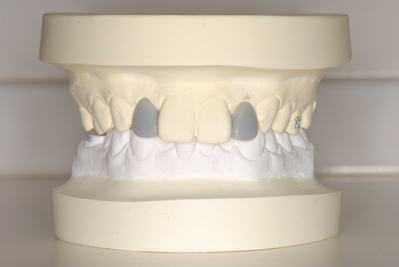

セットアップを作製。この時点でも患者さんと話し合い、TEK(仮歯)を作り、

患者さんが納得いく形を決めました。

セットアップ